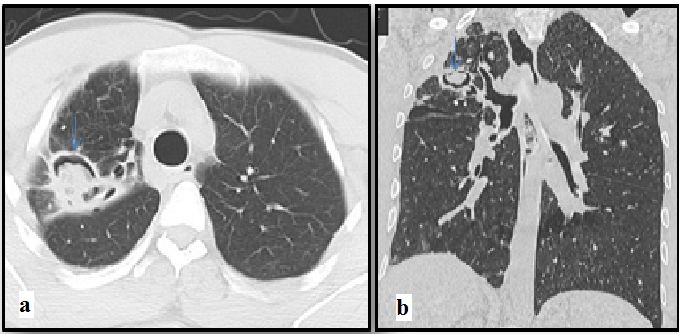

图7:轴向和冠状CT扫描显示空腔内的真菌球,与支气管扩张和多发小叶中央结节相关。

过敏性支气管肺曲霉菌病(ABPA)